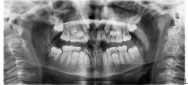

Dentición de transición

Los niños y adolescentes en dentición de transición requieren consideración especial del momento de erupción y del crecimiento facial. La falta de anclaje posterior durante la transición, dientes anteriores o posteriores en erupción, erupciones ectópicas y quistes de erupción contribuyen a la complejidad.